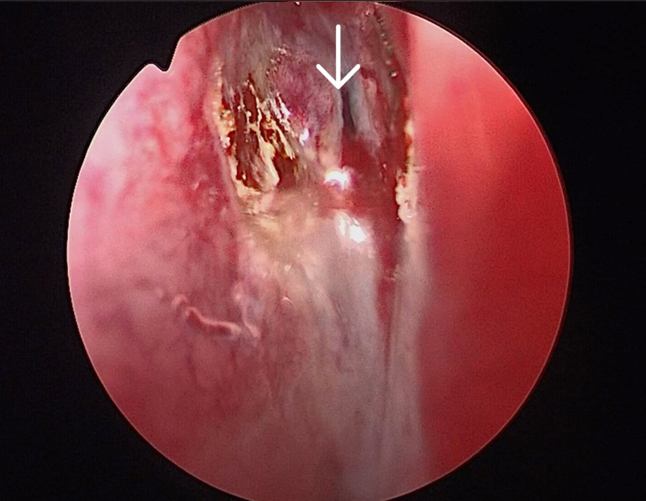

The surgery was performed under general anaesthesia by the first author. Nasal endoscopic examination after administering general anaesthesia showed watery discharge from the region of the left cribriform plate (figure3 B) and the left spheno-ethmoidal recess (figure 4). The surgery proceeded with left partial middle turbinectomy and widening of the sphenoid ostium on the left side. This was followed by left uncinectomy, middle meatal antrostomy, left anterior ethmoidectomy an removal of basal lamella and posterior ethmoidectomy. This was followed by clear delineation of the leak in the left cribriform plate and a wide sphenoidotomy (figure 5). The edematous sphenoid sinus mucosa was removed and the meningoencephalocele was seen in the left lateral recess above the vidian-rotundum line. The sphenoplalatine foramen was identified and the sphenopalatine artery cauterized. The medial aspect of the posterior wall of left maxillary sinus was removed partially. The upper part of the pterygoid process was drilled out and widened laterally exposing the antero-medial temporal lobe and the meningoencephalocele (figure 6) and the continuous csf leak leak identified.

Figure 3B. Arrow showing leak in the left cribriform plate